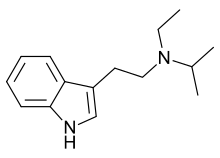

| EiPT | artificial | H | CH2CH3 | CH(CH3)2 | N-Ethyl-N-isopropyltryptamine | 848130-11-0 |